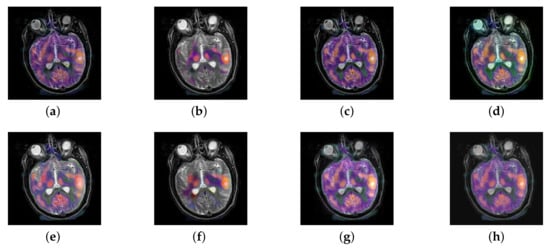

In this section, there are four image sets to fuse, each containing a MRI image and its corresponding CBF image in Figure 41. In Figure 42, Figure 43, Figure 44 and Figure 45, it can be seen that the structural information of fusion images obtained by our algorithm is complete. The color is not distorted, and the spectral features are natural. The fusion image based on DTCWT and NSCT algorithm have high color fidelity but less structural information. Other algorithms, such as IGM, LPSR, and FusionCNN, only focus on the structural information of the MRI image and ignore the color information of the fused image. Although the image structure information obtained by DDcGAN fusion algorithm is relatively complete, the edge of color information is not clear, which has a great influence on image contrast.

Figure 41.

Four pairs of MRI-cerebral blood flow diagram (CBF) source images: (a,c,e,g) are MRI images; (b,d,f,h) are CBF images.

Figure 42.

Fused medical images obtained by different algorithms (Figure 41a,b): (a) DTCWT, (b) GFF, (c) NSCT, (d) LPSR, (e) IGM, (f) FusionCNN, (g) DDcGAN, and (h) FusionNet.

Figure 43.

Fused medical images obtained by different algorithms (Figure 41c,d): (a) DTCWT, (b) GFF, (c) NSCT, (d) LPSR, (e) IGM, (f) FusionCNN, (g) DDcGAN, and (h) FusionNet.

Figure 44.

Fused medical images obtained by different algorithms (Figure 41e,f): (a) DTCWT, (b) GFF, (c) NSCT, (d) LPSR, (e) IGM, (f) FusionCNN, (g) DDcGAN, and (h) FusionNet.

Figure 45.

Fused medical images obtained by different algorithms (Figure 41g,h): (a) DTCWT, (b) GFF, (c) NSCT, (d) LPSR, (e) IGM, (f) FusionCNN, (g) DDcGAN, and (h) FusionNet.

The averaged subjective scores of MRI-CBF fusion images obtained by the above methods are shown from Figure 46 and Figure 47. Our fusion algorithm has obvious advantages in EN, FMI, SSIM, , , and AG from Figure 48, Figure 49, Figure 50, Figure 51, Figure 52, Figure 53, Figure 54, Figure 55, Figure 56 and Figure 57. Other metrics are inferior to those of FusionCNN, GFF, and LPSR fusion algorithm. However, as we have mentioned before, there may be inconsistency between subjective indicators and objective indicators, but this does not affect the assessment of image quality.